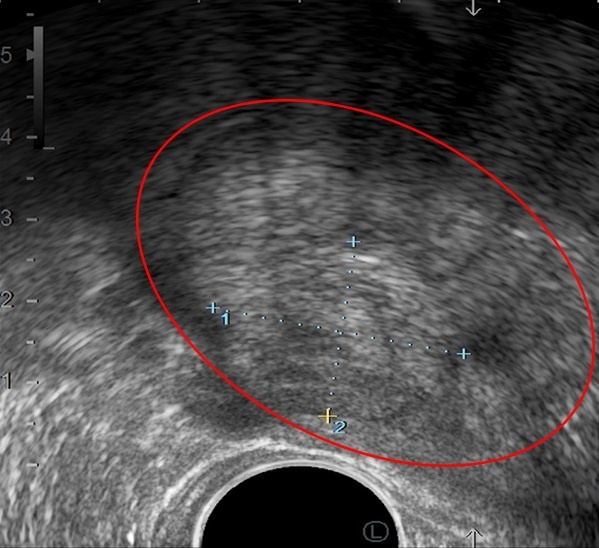

Hình ảnh khối u tuyến tiền liệt qua siêu âm. |

Thăm khám trực tiếp cho ông Hồng Liên là TS.BS Nguyễn Hoàng Đức (Trưởng khoa Tiết niệu - Trung tâm Tiết niệu - Thận học). Qua triệu chứng lâm sàng, bác sĩ siêu âm và sinh thiết tuyến tiền liệt. Kết quả cho thấy ông Liên bị phì đại lành tính tuyến tiền liệt. Tuy nhiên, thể tích của tuyến tiền liệt đến 240 ml, gấp 8 lần mức cho phép ở người lớn tuổi (thường 30-40 ml), lồi vào bên trong bàng quang, bít tắc đường thoát nước tiểu.